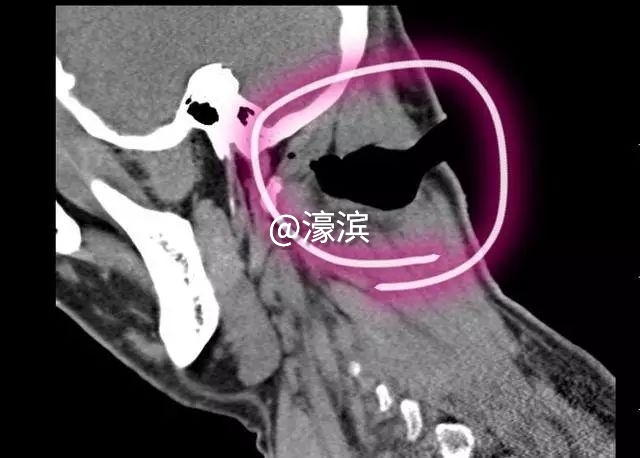

CT图上,患者的伤口

伤口像“贝壳”,血流止不住

患者陈某的伤口深达颈部的第一、二椎体,切断了多块肌肉,颈部内侧还有些许玻璃碎片残渣。

“只要一打开伤口进行更深入地检查判断,血就止不住的流淌,伤口部位血肉模糊,根本无法判断具体断裂血管的位置。”耳鼻咽喉-头颈外科朱新副主任医师介绍,大玻璃块把陈某的右颈部切成贝壳一样的开合状,可当头部摆放在正中间使伤口合上时不流血,头歪向左侧使伤口暴露后,颈部的血却像泉水一样汩汩流出。所以止血是一大难题,只有止住了血才能进行下一步判断。